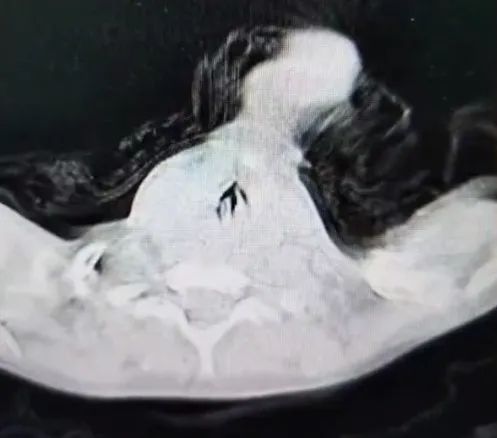

检查的CT显示,有异物堵塞了孩子的大部分气管。

切开气管后,医生从孩子的声门下小心翼翼地取出了异物。不看不知道,卡住孩子气管的,就是大家过年常吃的山核桃。